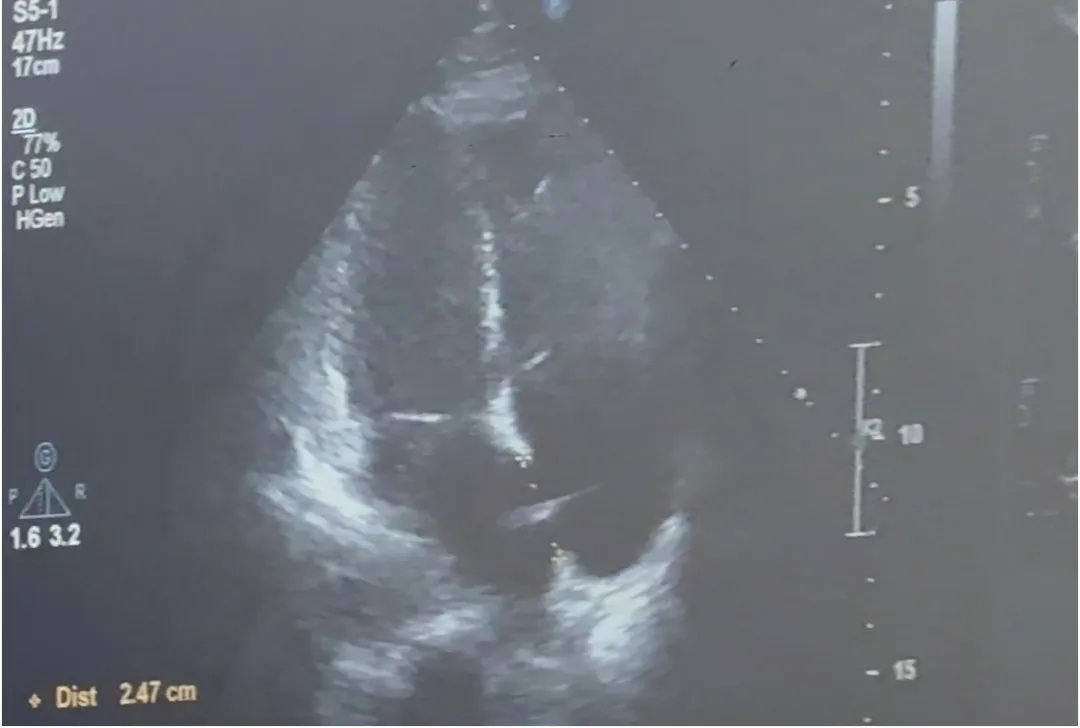

四腔心切面

合并房间隔膨出瘤

缺损+房间隔膨出瘤24.7mm